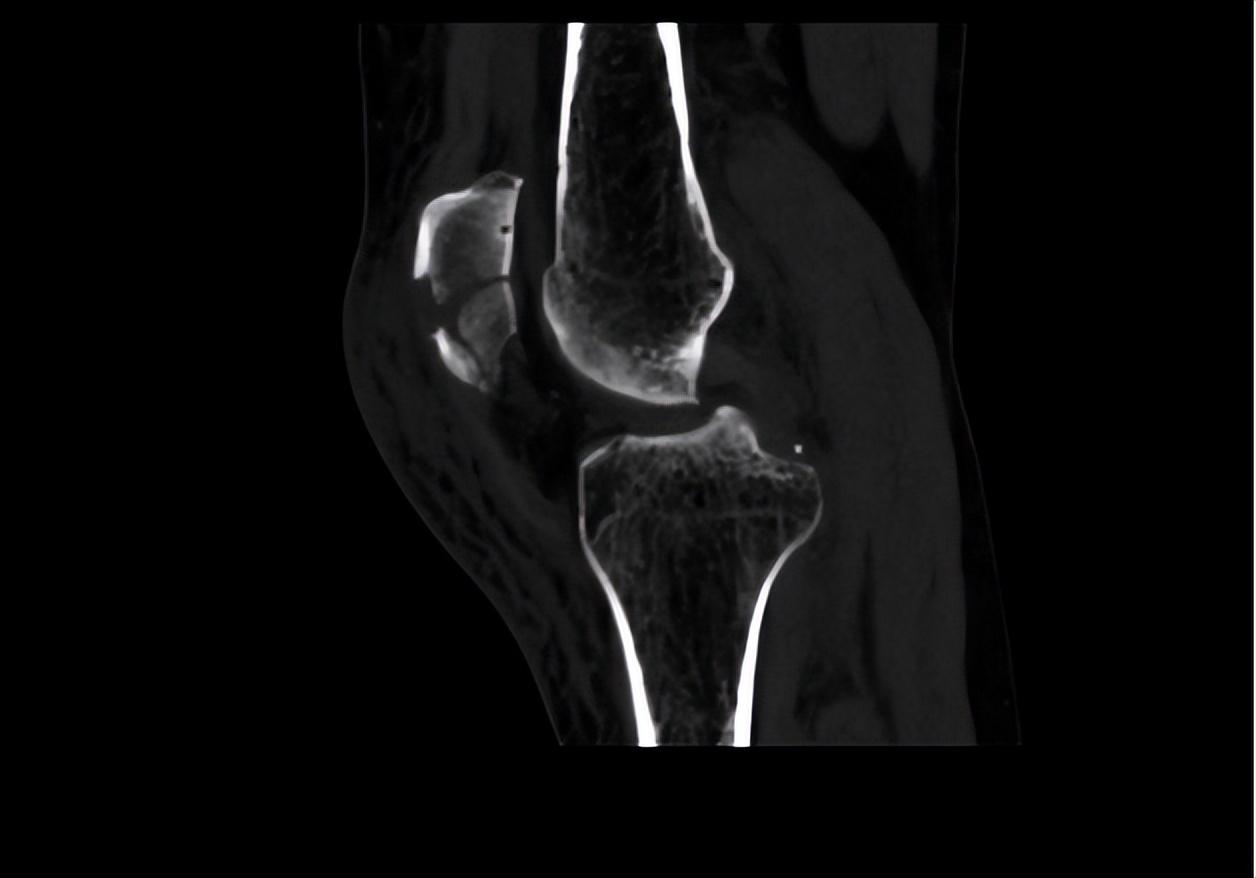

二、調(diào)節(jié)過程針對患者目前左髕骨骨折的情況,首要調(diào)節(jié)為進行手術(shù)調(diào)節(jié),所以待患者入院后,我立刻給她開了相關(guān)檢查,以排除手術(shù)禁忌。完善血常規(guī)、肝腎功、電解質(zhì)、大小便常規(guī)、凝血功能、輸血前檢查等均未見異常。同時我也讓患者完善了心電圖、彩超、CT檢查和X影像學檢查。雙下肢彩超提示:雙下肢動脈輕度輕度粥樣硬化。左膝關(guān)節(jié)平掃CT+二維、三維重建顯示:髕骨骨折,少量關(guān)節(jié)積液。心電圖未見異常。

術(shù)后第二天復查左髕骨X線提示:左髕骨骨折術(shù)后改變,可見金屬內(nèi)固定器影,斷端對位對線佳,骨小梁尚規(guī)則,左膝關(guān)節(jié)在位,關(guān)節(jié)間隙尚可。